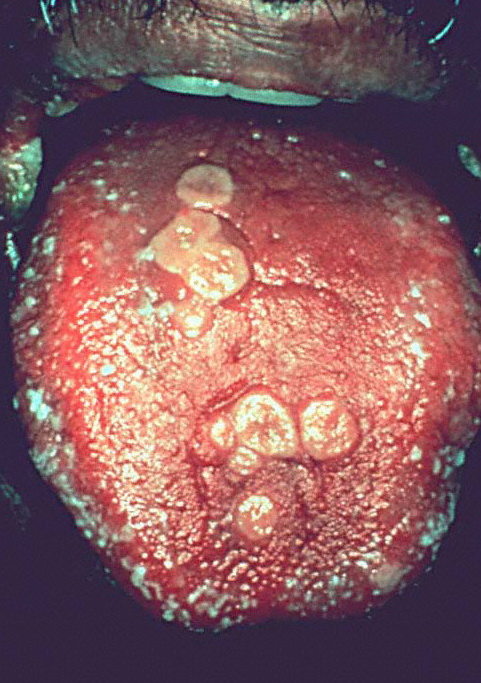

Oral herpes simplex -prim = العقبول البسيط الفموي الاولي